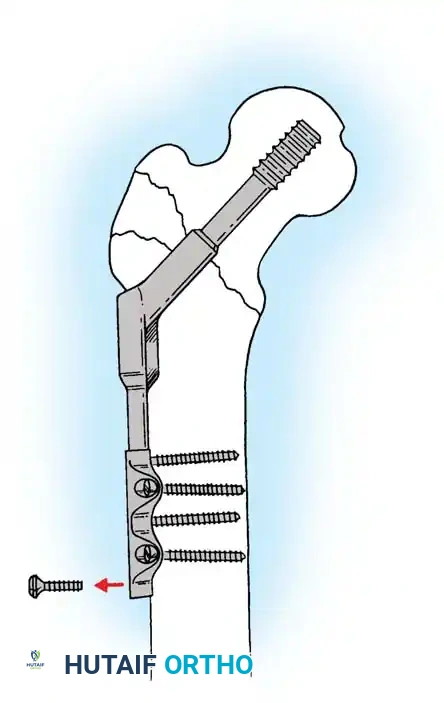

- Cephalomedullary Nail (CMN): The implant of choice for unstable patterns, particularly reverse obliquity (AO 31-A3) and fractures with subtrochanteric extension. The intramedullary position of the nail decreases the lever arm of the implant, reducing bending moments and the risk of hardware failure.

Biomechanical Pearl: In reverse obliquity fractures, an SHS is contraindicated. The sliding mechanism of the SHS allows the femoral shaft to medialize uncontrollably due to adductor pull, leading to catastrophic failure. A cephalomedullary nail acts as a lateral buttress, preventing this medialization.

5. Intramedullary Nailing (For Unstable Fractures)

If a cephalomedullary nail is chosen, the entry point is established at the tip of the greater trochanter (or slightly medial, depending on the specific implant design).

Insertion of the cephalomedullary nail down the femoral shaft. Care must be taken not to distract the fracture site during insertion.

After the nail is seated, the proximal lag screw(s) are inserted through the nail into the femoral head, adhering to the same TAD principles.

Proximal locking of the cephalomedullary nail. The targeting guide ensures accurate trajectory into the femoral neck.

Finally, distal locking screws are placed to control rotation and maintain length.

Final fluoroscopic evaluation confirming anatomical reduction, optimal implant placement, and restoration of the neck-shaft angle.